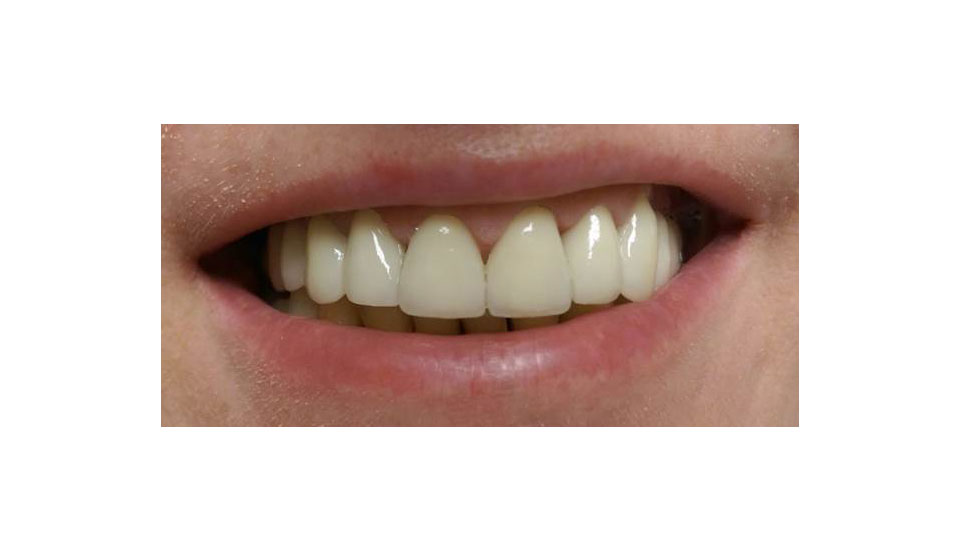

Teljes szájüregi rehabilitáció két lépésben

Ismét egy teljes szájüregi rehabilitáció két lépésben. Először az alsó fogak lettek kihúzva és azonnal implantálva, híddal ellátva, majd később a felső. IHDE svájci azonnal terhelhető implantátumok és cirkónium hidak. Dr. Kelemen Péter és a Symbion Fogtechnika közös munkája.